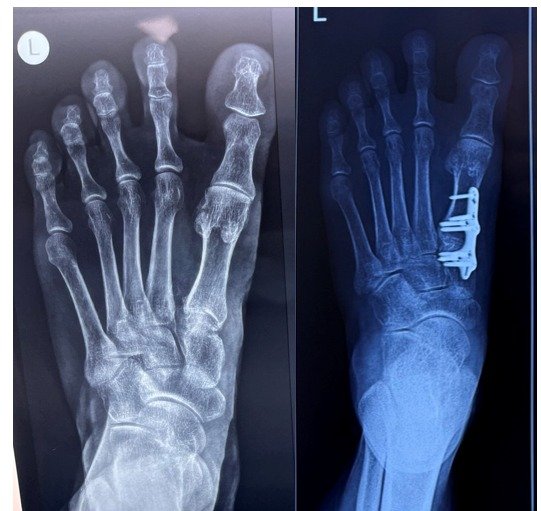

Bunion

Bunion surgery, also known as bunionectomy or hallux valgus correction surgery, is a surgical procedure performed to correct a bunion. A bunion is a bony…